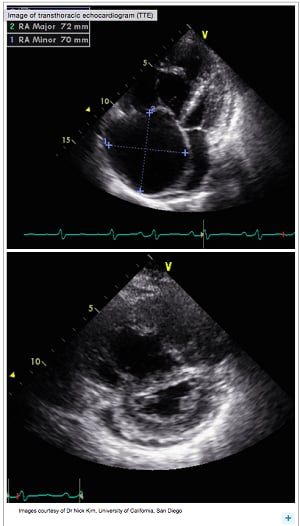

A transthoracic echocardiogram (TTE) helps physicians evaluate patients with suspected pulmonary hypertension (PH)1:

Signs of PH with echocardiogram

The following findings suggest PH1:

Right ventricular dilatation or overload

Right atrial enlargement, hypertrophy, and hypokinesis

Tricuspid regurgitation

An echocardiogram may be performed 6 weeks after acute pulmonary embolism (PE) to screen for persistent PH that may predict the development of chronic thromboembolic pulmonary hypertension (CTEPH).2